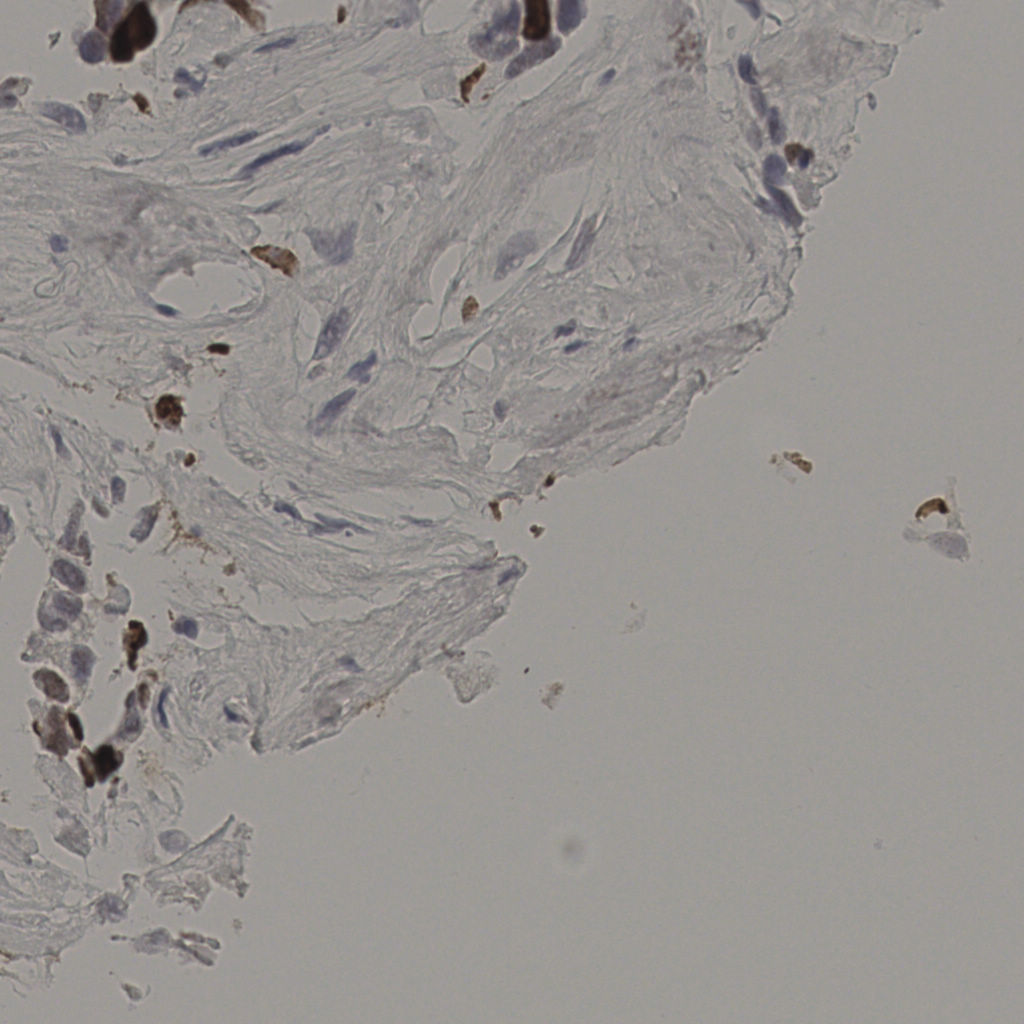

切片统计

总切片 2640

有效 412

已标记 412

有效率 16%